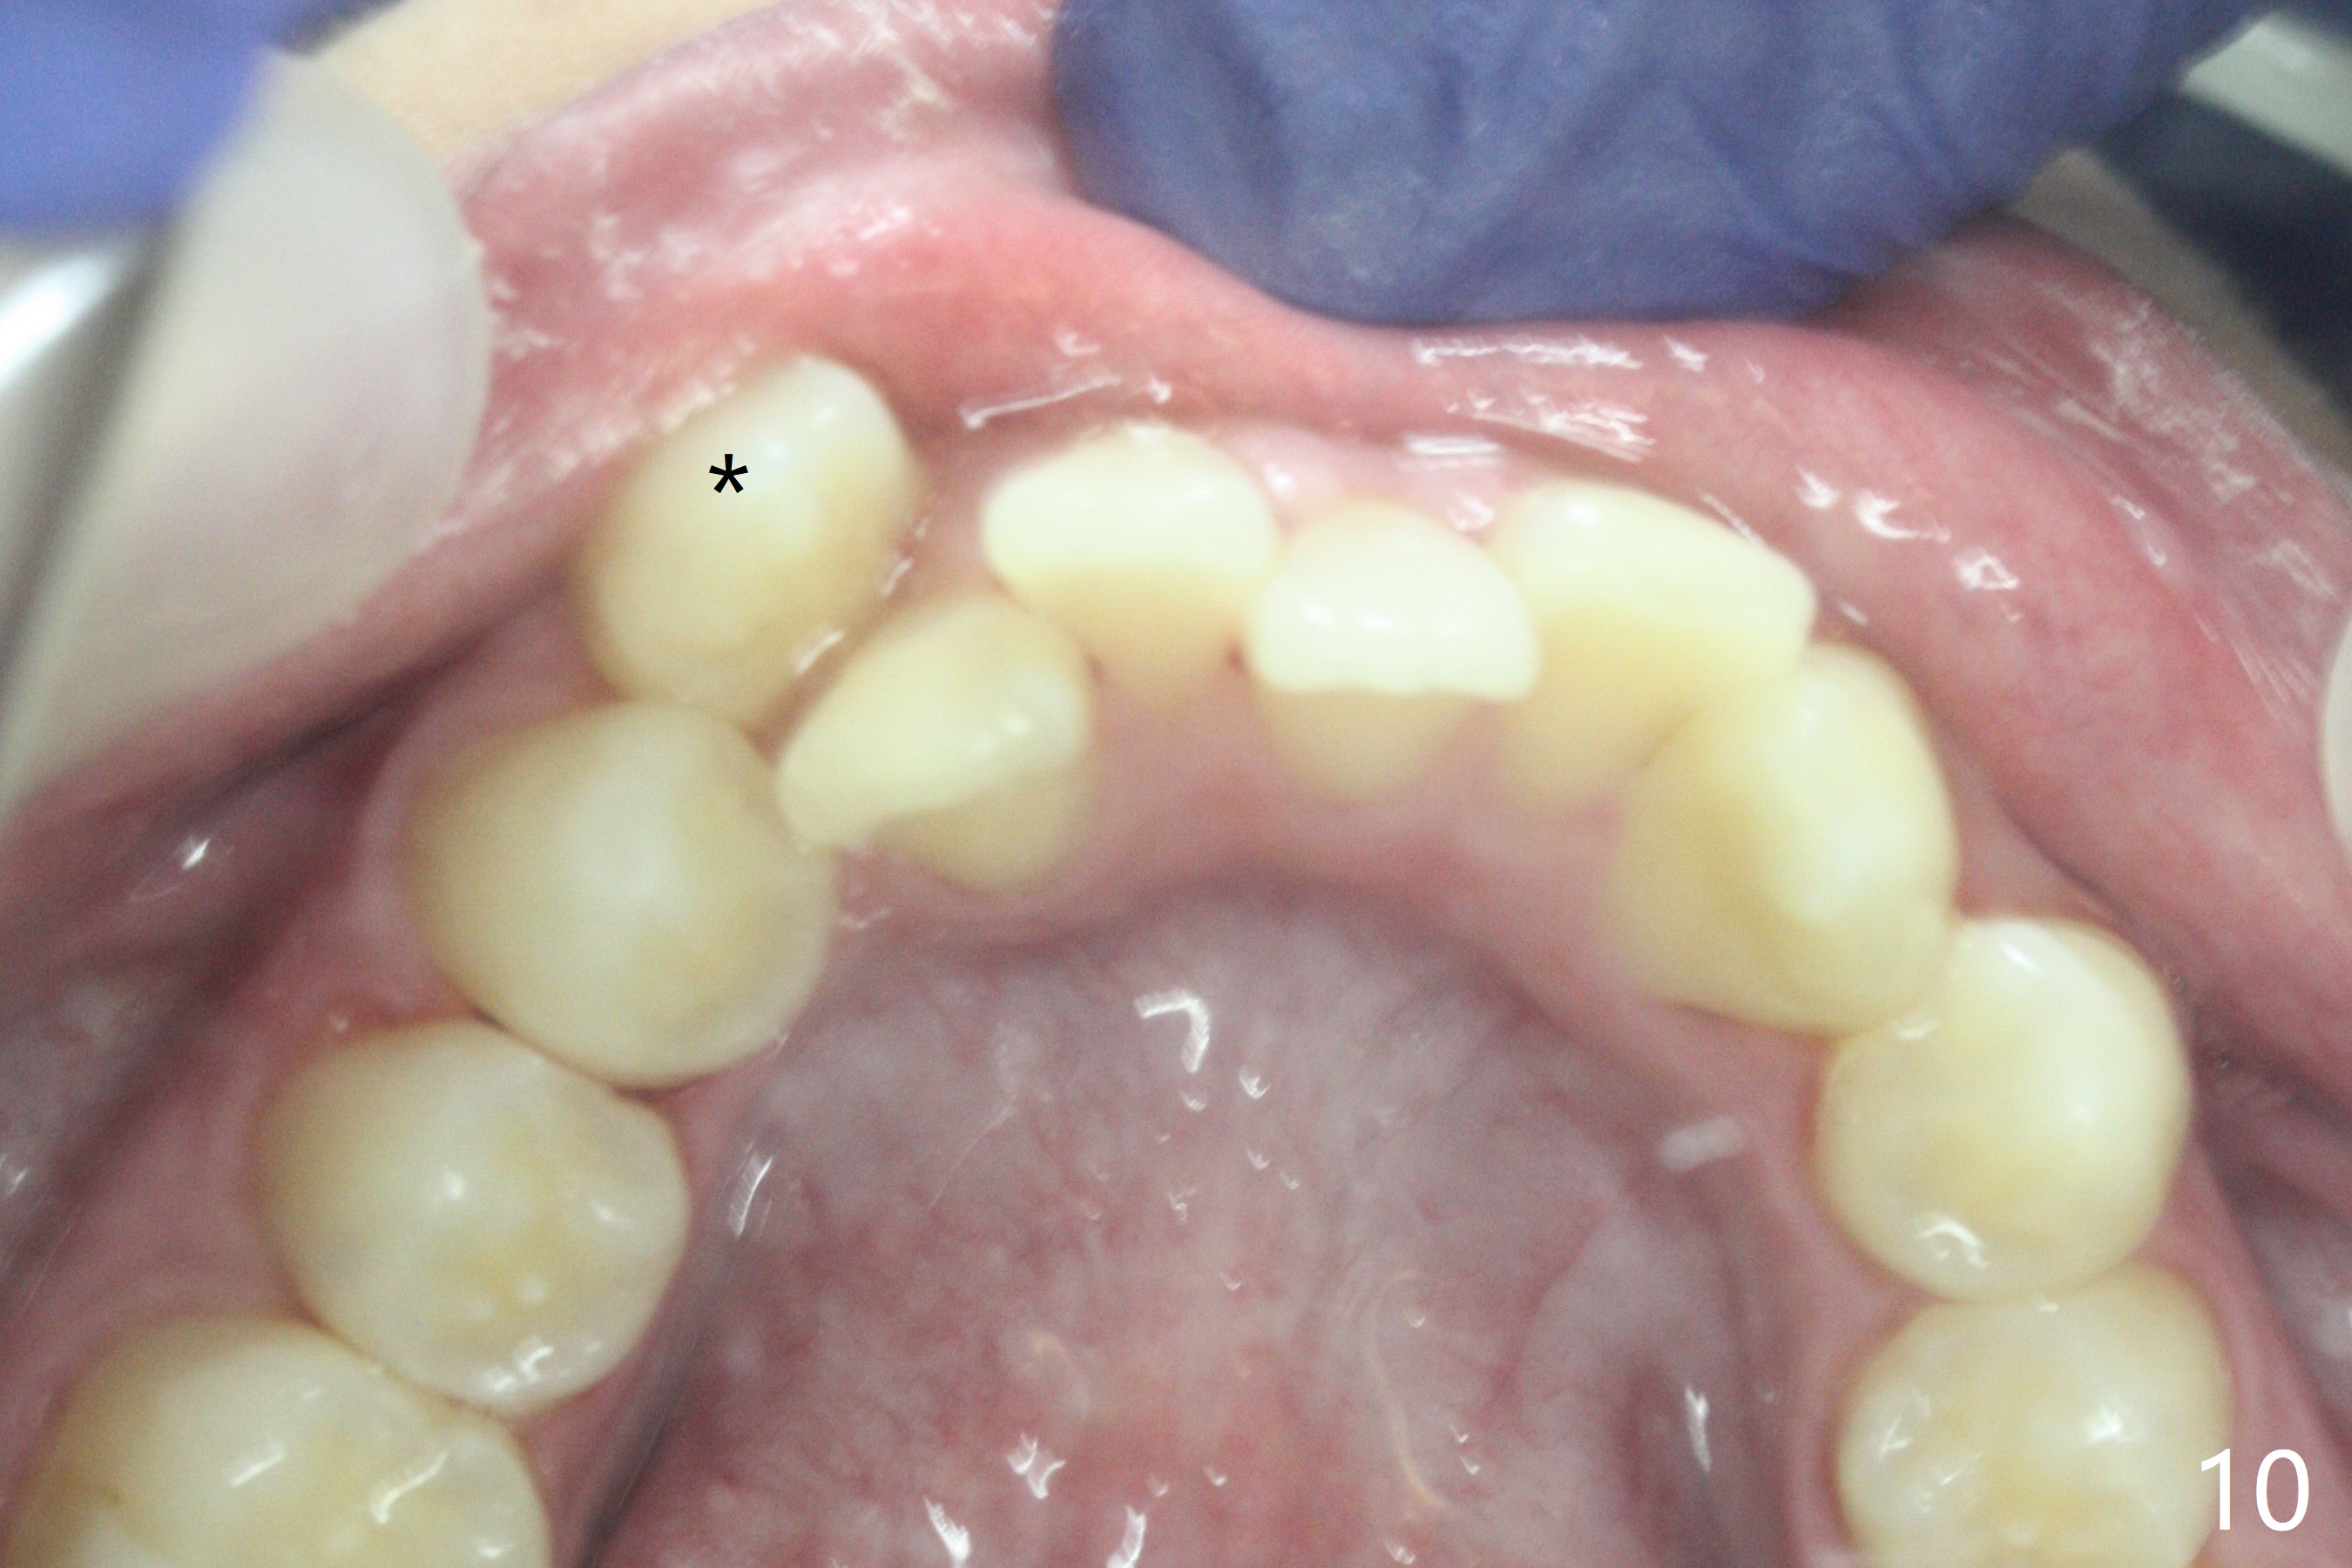

Complete buccoversion of LR 3 (Fig.10 (mirror view) 8).